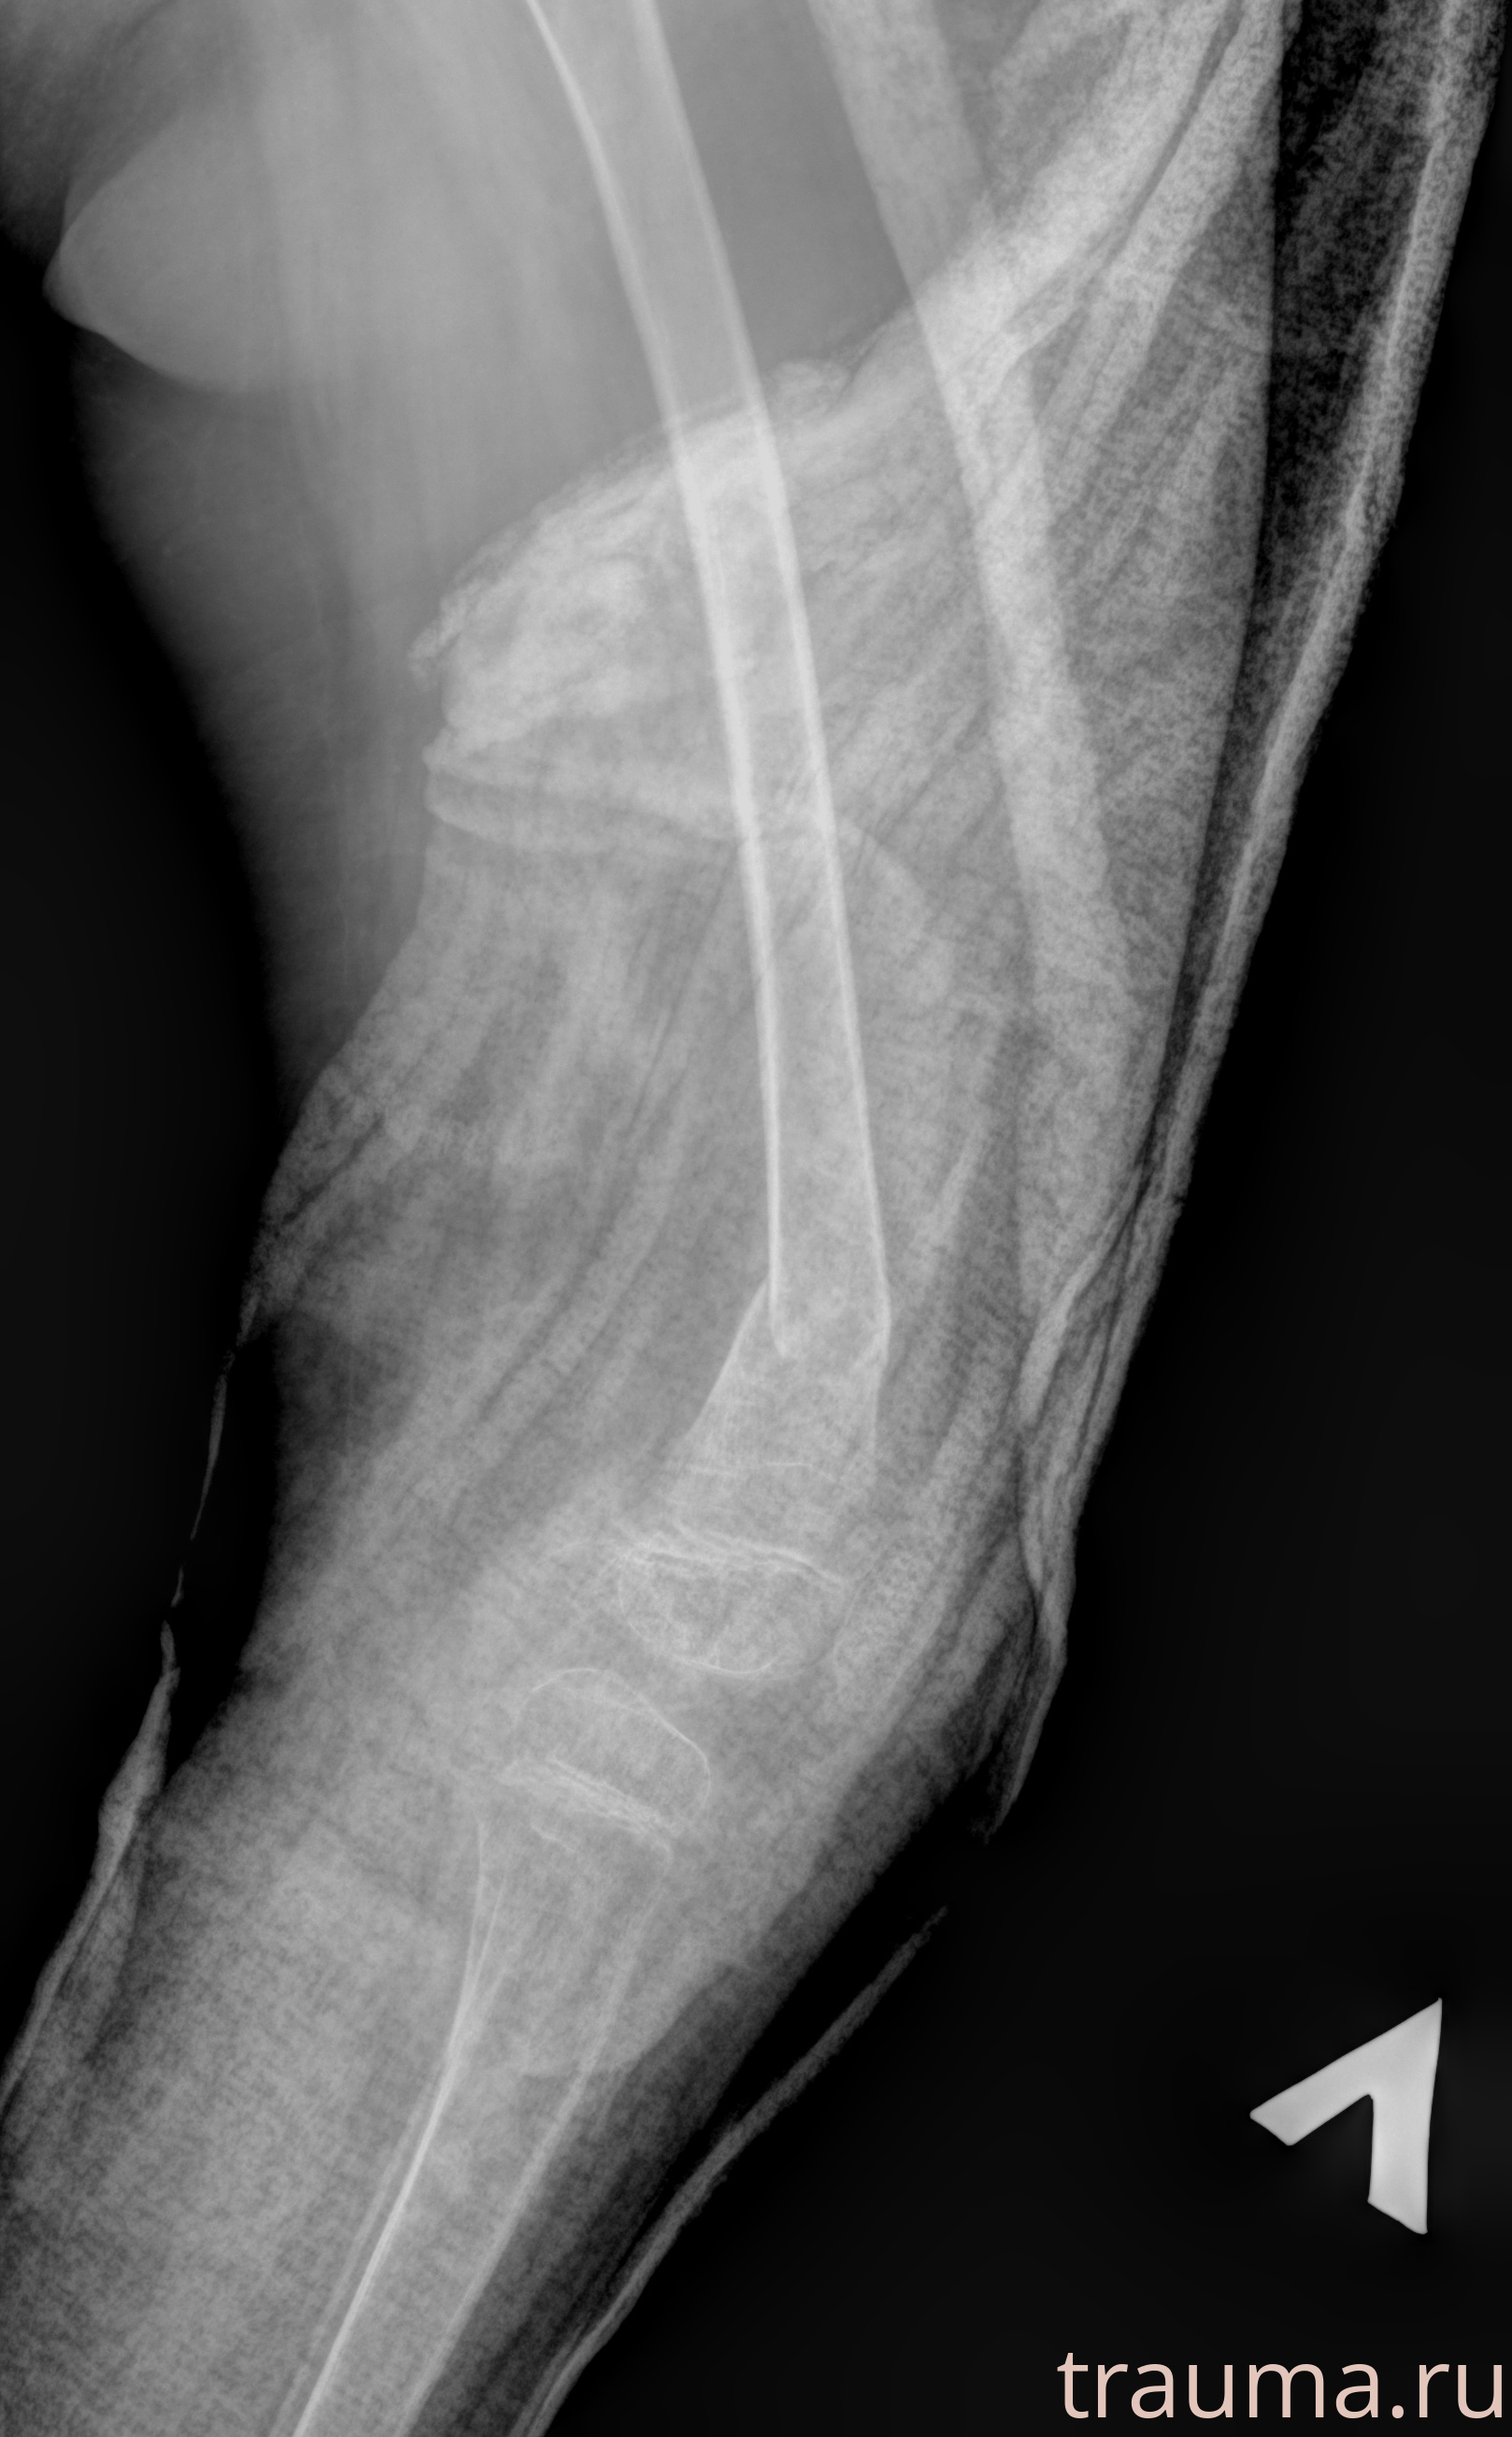

Рентгенограммы